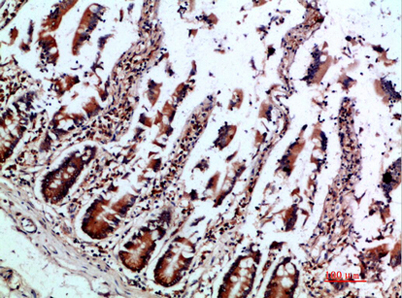

Immunohistochemical analysis of paraffin-embedded human-colon, antibody was diluted at 1:200

Immunohistochemical analysis of paraffin-embedded human-colon, antibody was diluted at 1:200 -

Immunohistochemical analysis of paraffin-embedded human-colon, antibody was diluted at 1:200

Immunohistochemical analysis of paraffin-embedded human-colon, antibody was diluted at 1:200